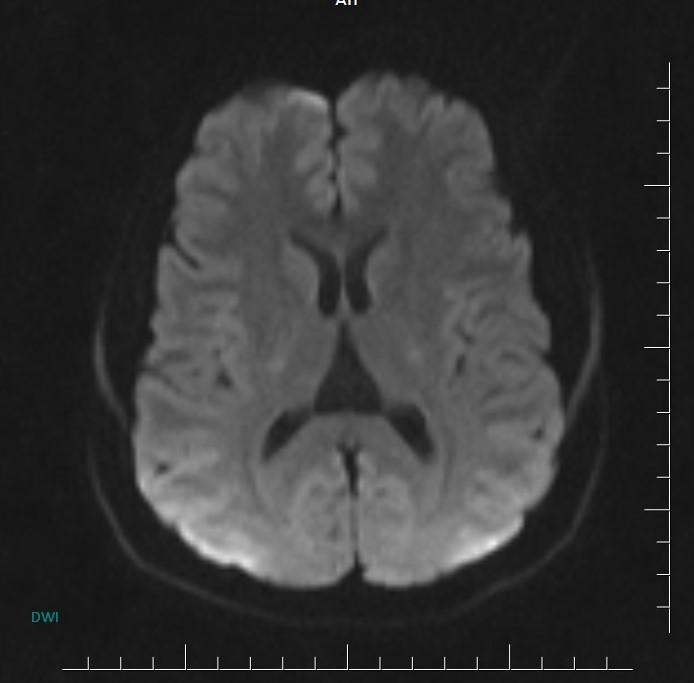

MR images incidentally revealed a triangular-shaped CSF space between the lateral ventricles (arrows).

Axial MR/CT image shows a triangular-shaped CSF space situated behind the foramen of Monro, between the lateral ventricles. Coronal image demonstrates the elevated and splayed fornices.